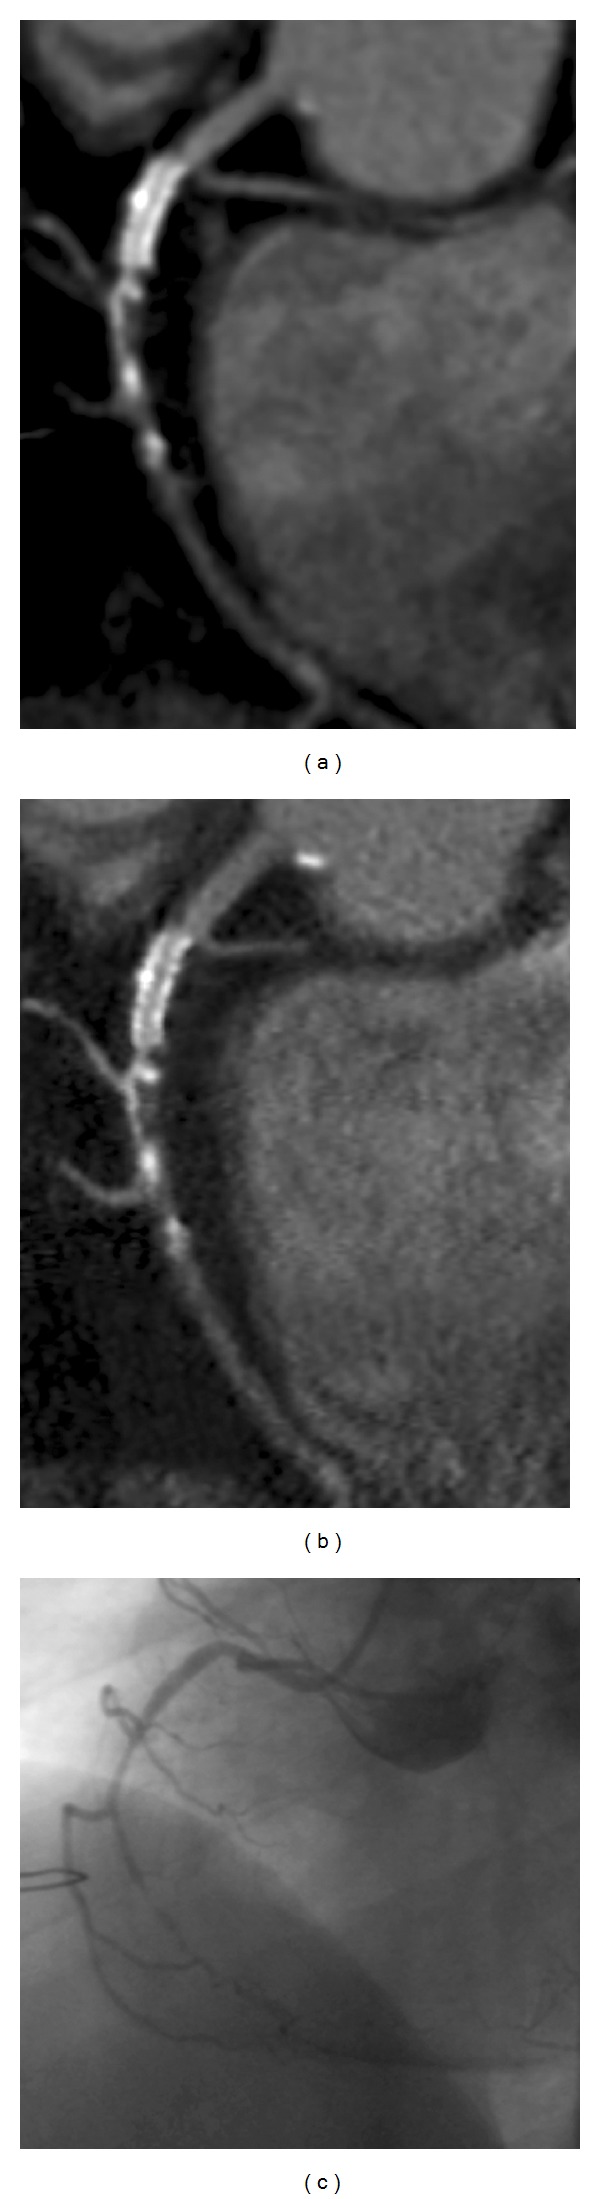

Coronary stenting became a mainstay in coronary revascularization therapy. Despite tremendous advances in therapy, in-stent restenosis (ISR) remains a key problem after coronary stenting. Coronary CT angiography evolved as a valuable tool in the diagnostic workup of patients after coronary revascularization therapy. It has a negative predictive value in the range of 98% for ruling out significant ISR. As CT imaging of coronary stents depends on patient and stent characteristics, patient selection is crucial for success. Ideal candidates have stents with a diameter of 3 mm and more. Nevertheless, even with most recent CT scanners, about 8% of stents are not accessible mostly due to blooming or motion artifacts. While the diagnosis of ISR is currently based on the visual assessment of the stent lumen, functional information on the hemodynamic significance of in-stent stenosis became available with the most recent generation of dual source CT scanners. This paper provides a comprehensive overview on previous developments, current techniques, and clinical evidence for cardiac CT in patients with coronary artery stents.